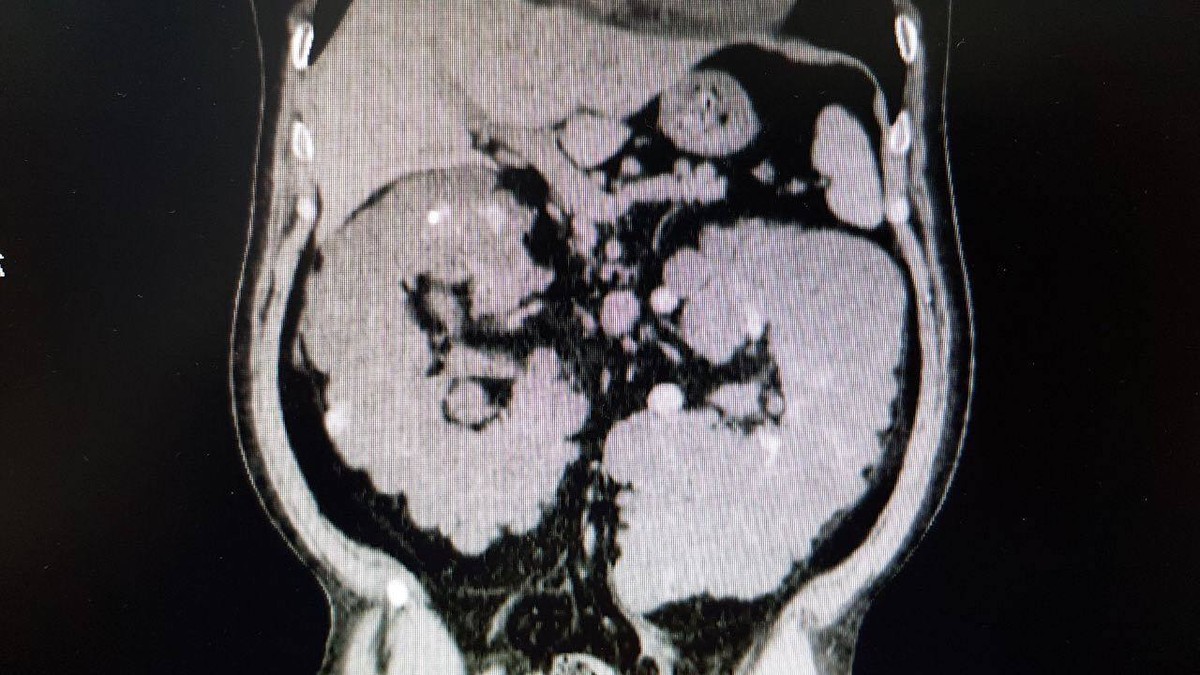

استئصال كليه متكيسه كبيره في المستشفي السعودي الألماني بالرياض

تمكن الفريق الطبي بقسم المسالك البولية بالمستشفى السعودي الألماني بالرياض من استئصال الكليه اليسري متعدده الأكياس بحجم يتجاوز ٣٠ سنتيمتر.

و كان المريض صاحب ال٤٨ عام يعاني من الآلام شديده في البطن مع ارتفاع بدرجه الحراره.

و باجراء الفحوصات تبين وجود أكياس متعدده ممتلئة بالصديد و التجمعات الدموية، و تم استئصال الكليه اليسري بنجاح علما بأن المريض كان يقوم باجراء الغسيل الكلوي المستمر.